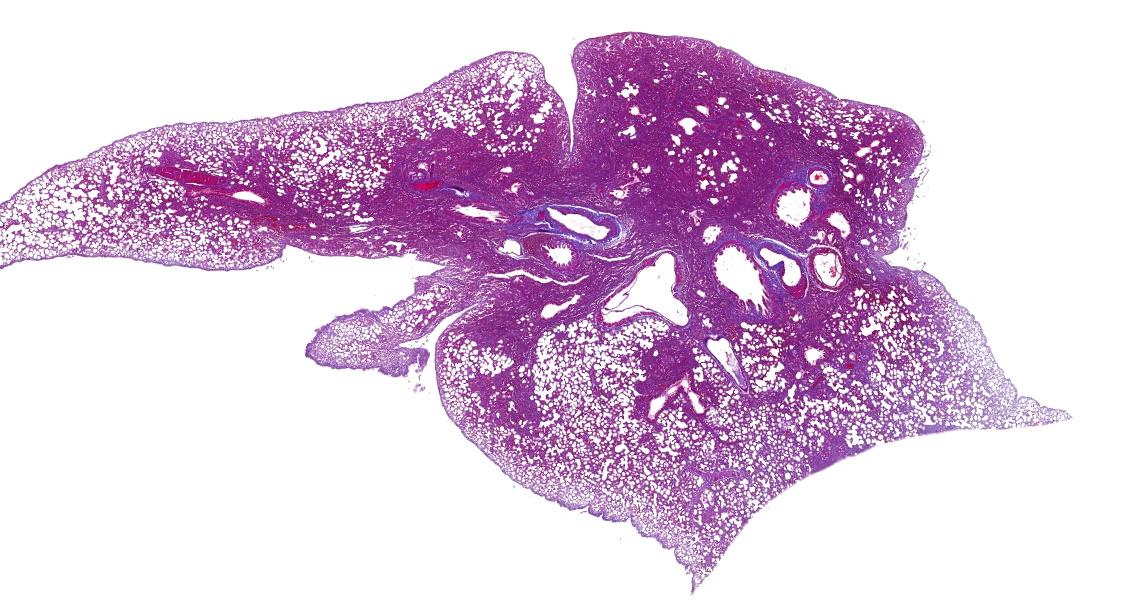

子宮Masson染色

Masson染色